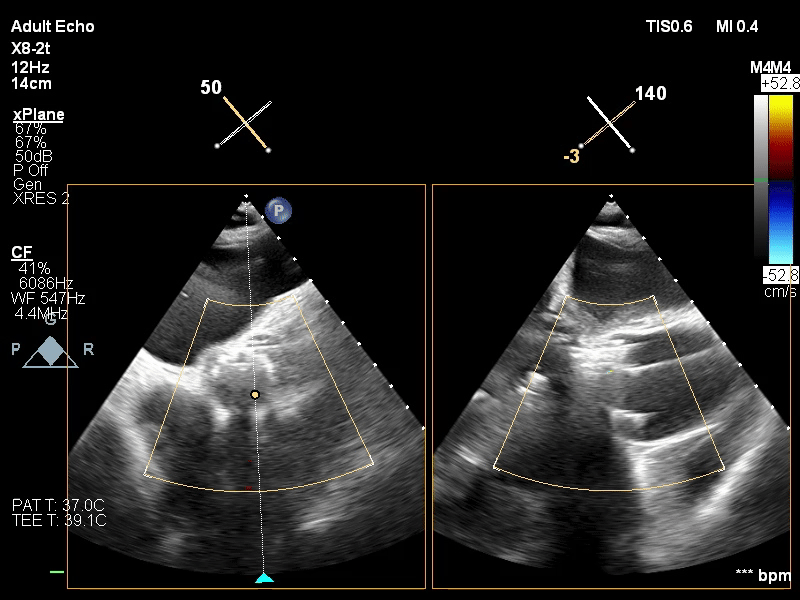

经过术前测量和分析,李伟栋教授团队结合患者的中央型反流伴有后隔长裂隙的情况定下手术策略,即在后瓣靠近隔瓣的位置,植入K-Clip®,进行后瓣偏隔瓣环的缩环成形,以期改善反流。

患者全麻后,右侧颈静脉穿刺,将K-Clip®输送系统送达右心房内。在超声医生指引下,将K-Clip®锚定件到位,打开夹持臂,对靶位进行夹合。

手术中,术者充分考虑了器械植锚定点须避免对冠脉和传导束的影响,适时地调整了手术策略,在后瓣与隔瓣交界处找到了理想的锚定靶点,仅用一枚K-Clip®夹子,就将三尖瓣反流从术前的重度(4级),下降为微量(0~1级),几乎没有反流。心脏团队和主持专家对反流减少程度非常满意,遂解离夹合件,退出输送系统。

术后评估冠脉血流通畅,生命体征稳定,伤口无出血,即结束手术。手术在30分钟的直播时间内完成。